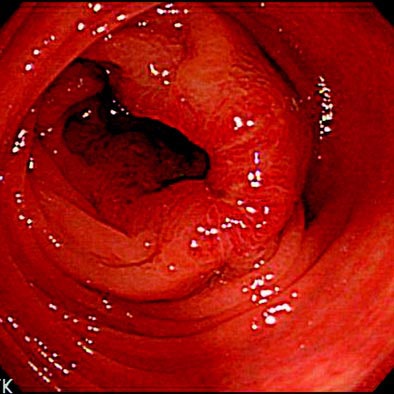

| Above, colonoscopic view and surface and vascular virtual endoluminal images for representative case of advanced colorectal cancer in a 60-year-old woman. Colonoscopic view shows advanced cancer in sigmoid colon. Below, surface virtual endoluminal view in the same patient shows lesion. Bottom, vascular virtual endoluminal image clearly shows blood pooling of tumor and vessels. Iinuma G, Moriyama N, Satake M, Miyakawa K, Tateishi U, Uchiyama N, Akasu T, Fujii T, Kobayashi T, "Vascular Virtual Endoluminal Visualization of Invasive Colorectal Cancer on MDCT Colonography" (AJR 2005; 184:1194-1198). |